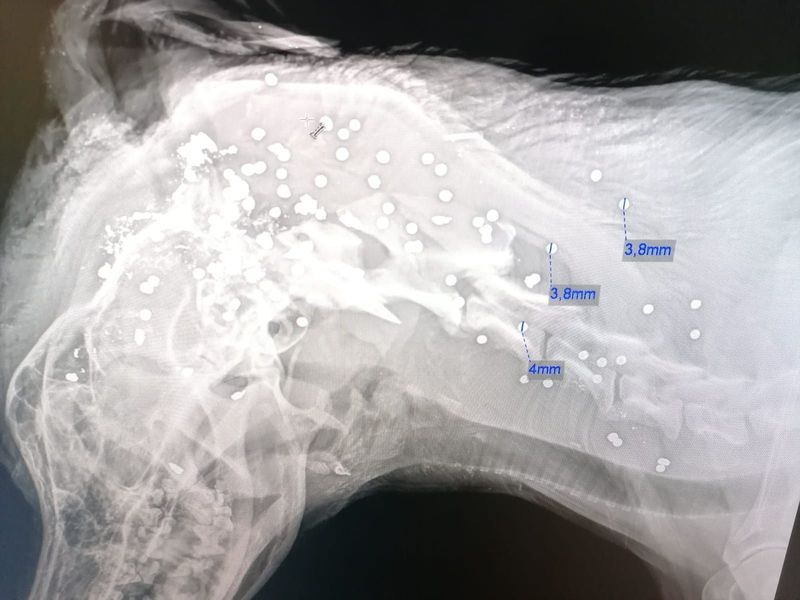

Emil wurde von Dutzenden Schrotkugeln getroffen.

Amtstierarzt Kutschera